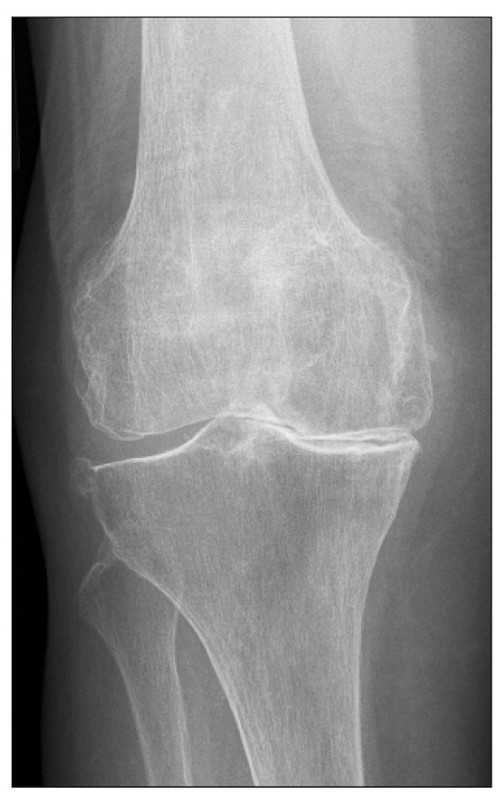

A 72-year-old female presents to an outpatient clinic with a chief complaint of chronic bilateral knee pain that has progressed over the past few years. She describes the pain as a dull ache, worse with prolonged standing, walking more than a block, and descending stairs. The pain is consistently relieved by rest, and she experiences transient morning stiffness lasting less than 15 minutes. She occasionally notices a grinding sensation in her knees. Her medical history includes well-controlled essential hypertension and obesity, with a body mass index (BMI) of 31 kg/m². On physical examination, there is mild valgus deformity bilaterally, palpable crepitus noted with passive range of motion, and tenderness along the medial joint lines. Flexion is limited to 110 degrees (normal 135 degrees) and extension to -5 degrees (normal 0 degrees). There is mild bony enlargement of both knees but no warmth, erythema, or significant effusions. Considering her clinical presentation, what is the most likely diagnosis and the appropriate initial management strategy?